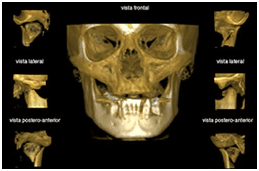

Tomografia computadorizada Reconstruções 3D

Avaliação de patologias (frontal) Avaliação de patologias (lateral)

Avaliação de patologias (horizontal)